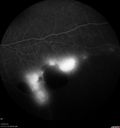

51 year old male with a broken vein in the left eye. His vision is pretty good. He has not noticed any vision change. You asked him to come here for further evaluation in the left eye. VA OD: sc20/63 PH20/25-2 NccJ1 VA OS: sc20/20 Patient had scatter laser to non-perfused retina and never had a vitreous hemorrhage (yet)

Coats' Disease -51 year old asymptomatic male450 views20/20 vision - had laser to non-perfusion because of proliferation.00000